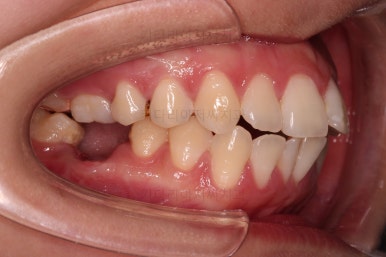

장치를 부착해서 가지런하게 하고요.

발치가 필요한 치아를 하나씩 뽑아나갑니다.

어금니 발치 공간이 어마어마하게 넓죠?

저 공간만큼 앞니가 들어가도록 하면 큰일납니다. 입이 너무 많이 들어가게 됩니다.

따라서 매우 신중한 테크닉으로 입매 조절을 잘 해야 합니다.